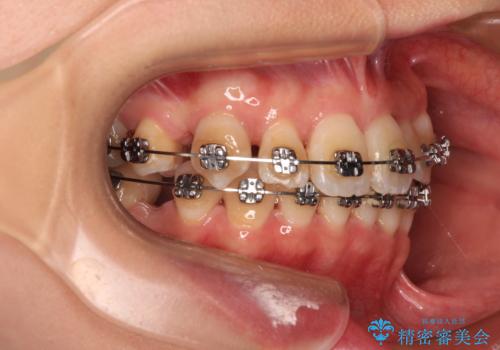

- 矯正装置

- メタルブラケット

- 前歯1本が後ろ側に隠れてしまうほどのデコボコを気にして来院された患者様です。

前歯のデコボコが顕著なのはもちろんですが、左右ともに奥歯の咬み合わせに問題があり、上顎臼歯が前方位にある状態でした。

上顎は左右の第一小臼歯2本を、下顎は左右第二小臼歯2本を抜歯することで、奥歯の咬み合わせを改善しながら、デコボコを解消していくこととしました。